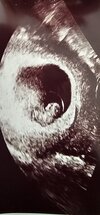

No to dziewczynki , ja lecę na wizytę i sie wszystko okaże czy jest serduszko i czy wszystko jest w porządku. Dam znac po wizycie.

Jestem już po wizycie , maluszek rośnie bardzo ładnie ma 11,4 cm , serduszko bije , krwiak się zmniejszył, jest ulga na sercu. Następna wizyta 09.05.

Który masz tydzień, że dzidzia tyle już ma cm ?Jestem już po wizycie , maluszek rośnie bardzo ładnie ma 11,4 cm , serduszko bije , krwiak się zmniejszył, jest ulga na sercu. Następna wizyta 09.05.![]()

7+6 tc termin na 9 grudniaKtóry masz tydzień, że dzidzia tyle już ma cm ?